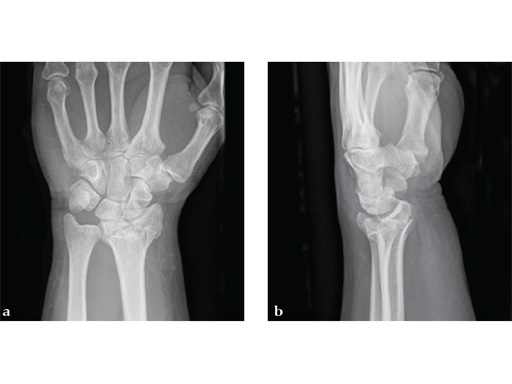

Case 2: A 44-year-old man sustained polytrauma following a car accident. Among his injuries was a distal radial fracture, Mller AO Classification 23-C1.

Case provided by Vitezslav Ruber, Brno, Czech Republic